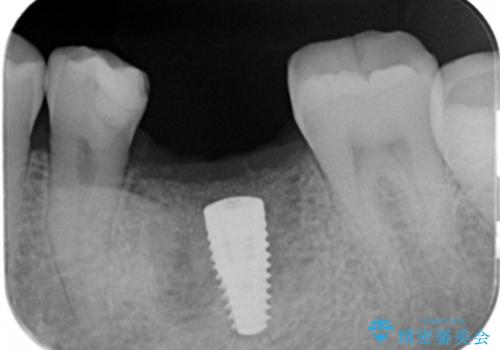

- 歯を破折により失い、インプラント治療を希望され来院されました。

インプラントを埋入し咬合機能を回復するとともに周囲の骨造成も同時に行っていきます。

インプラントを適切な位置に埋入することで、清掃性が高くしっかりと咬合力に耐えられるようなインプラント治療を行うことができます。